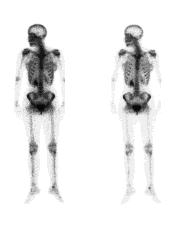

A DEXA scan is a low-radiation x-ray that measures the density of the minerals in your bones. Usually, it measures density in the spine and hip bones. Your health care provider uses this test to:

·         Diagnose bone loss and osteoporosis

·         Predict your risk of future bone fractures

·         See how well osteoporosis medicine is working

A simple spine or hip x-ray may show fracture or collapse of the spinal bones. However, simple x-rays of other bones are not very accurate in predicting whether you are likely to have osteoporosis. A new low-radiation spine x-ray called a vertebral fracture assessment (VFA) is now often done with a DEXA to better identify fractures that do not have any symptoms.

DEXA scan results compare your bone mineral density with both a young adult who has no bone loss and with people your age and gender. This means that at age 80, almost one third of women with normal age-related bone loss would have osteoporosis, based on their DEXA scan results.